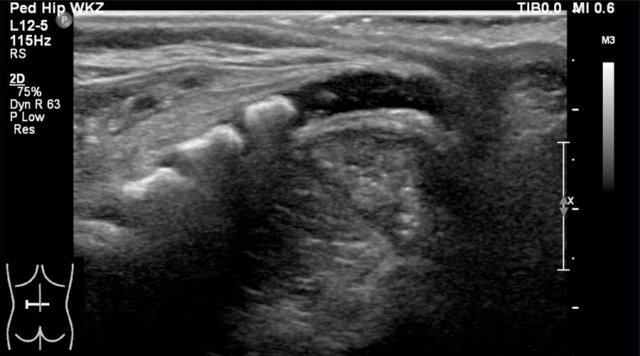

The spinal cord is depicted as a very hypoechoic structure with a central echogenicity.

This central echogenicity is supposed to represent the interface between the anterior commissure and the median anterior fissure, and not the central canal.

Axial image of the spinal cord with central echogenicity.